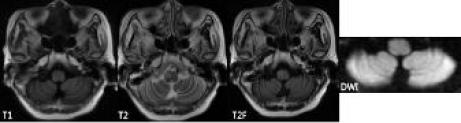

顱腦MRI示:延髓偏右側(cè)異常信號(hào),考慮肥大性下橄欖變性(見(jiàn)圖2)。

診斷:肥大性下橄欖核變性(Hypertrophic olivary degeneration, HOD)、Holmes震顫。

特征性MRI表現(xiàn)為延髓腹外側(cè)下橄欖核區(qū)局限性T2WI高信號(hào)、T2Flair稍高或高信號(hào)、T1WI等或稍低信號(hào)、DWI等信號(hào),一般無(wú)增強(qiáng)效應(yīng),伴或不伴下橄欖核體積增大。這與發(fā)病時(shí)間有關(guān),一般原發(fā)病1月后僅表現(xiàn)為延髓腹外側(cè)T2WI高信號(hào),4~6月后可出現(xiàn)下橄欖核增大,3~4年后下橄欖核恢復(fù)正常體積或萎縮。